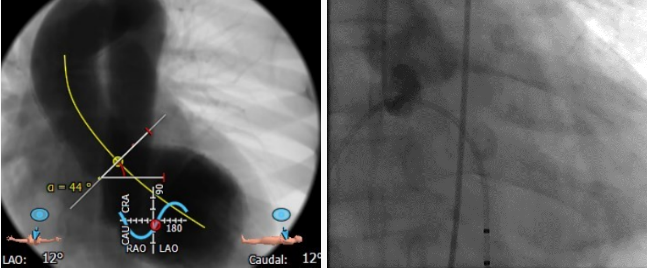

体位选择

选取合适的投射角度,三个窦底部在一个平面上,同时无冠窦在最低点

可以术中造影确认角度是否合适

术中影像

主动脉根部造影

导丝跨瓣

选择BaIt23球囊进行预扩

结合术前CT判断和术中影像判断,最终决定植入L26号venus A瓣膜。采取标准位置释放。